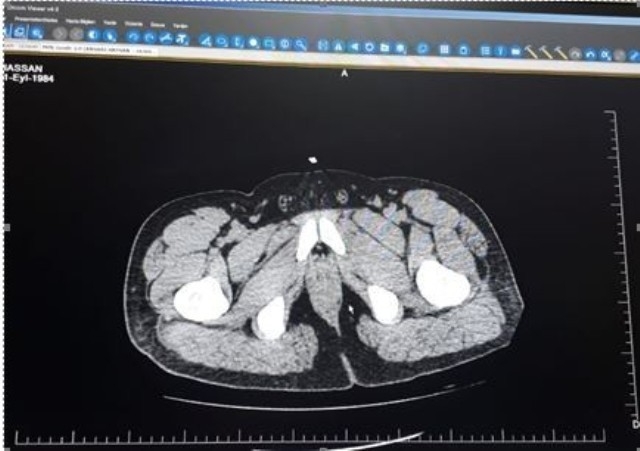

Denizli İl Emniyet Müdürlüğü'ne bağlı Narkotik Suçlarla Mücadele Şube Müdürlüğü ekipleri 2019-2020 eğitim öğretim yılının başlamasına sayılı günler kala kent genelindeki güvenlik tedbirlerini arttırdı. Narkotik ekipleri uyuşturucu madde suçlarıyla mücadele alanındaki çalışmalarını da hız kesmeden devam ediyor. Özellikle kent merkezinde vatandaşların yoğun olarak yer aldığı alanlarda ve Pamukkale Üniversite bölgesinde uygulama ve kontrol faaliyetleri gerçekleştiren narkotik ekipleri sokak satıcılarına da göz açtırmıyor. Bu kapsamda son olarak gerçekleştirdikleri başarılı operasyon ile İran'dan, Denizli'ye yutma yöntemiyle eroin maddesi taşıyan H.A., isimli şahıs ve Denizli'de bağlantılı olduğu kişileri yakalayan narkotik ekipleri 250 gram eroin yakalandı. Şüphelinin midesinde bulunan yutma tekniği için özel ambalajlanmış eroin paketleri hastanede uzman personel tarafından tıbbi müdahale ile çıkartıldı.